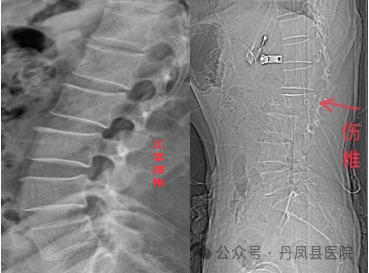

据悉,49岁的何先生因骑三轮车不慎摔伤,伤后即感腰部疼痛剧烈,翻身困难,不能站立,双下肢活动障碍,会阴部感觉丧失,双下肢感觉麻木,排大小便障碍,被家人紧急送至我院骨三科救治。科室值班医生何正位大夫立即为患者进行查体,经查体,发现患者腰部压痛,以腰1、2棘突压痛明显,腰部主被动活动受限,双下肢活动、感觉障碍,且不时叫嚷腰部疼痛,神情十分痛苦。临床经验丰富的何大夫进一步为患者进行腰部CT和磁共振检查,诊断为:腰2椎体爆裂骨折、滑脱并椎管Ⅲ度狭窄,腰1椎体压缩性骨折。 ![]()

何医生介绍到:“患者腰2椎体为爆裂性骨折,累及椎体的前柱、中柱和后柱,已经严重压迫到周围神经,因受损椎体及相应节段脊髓受压,导致患者下肢无法活动,受损腰椎如不及时手术固定,腰椎周围神经受压会持续加重,不但影响治疗,还极易给患者造成二次伤害,但患者腰2椎体周围神经丰富,若手术中稍有不慎,甚至造成患者瘫痪,手术风险高,难度大。一刻也不能耽搁,必须尽快确定手术方案,当时就立即向科主任汇报了患者的情况。”虽在元旦假期,张丹生主任立即赶至病房查看了患者。为了尽快解除脊髓压迫、减轻骨折二次伤害,张丹生主任立即组织科室团队为患者研究手术方案,从围术期管理、术中操作、术后护理及康复等方面下手,精心设计手术、护理方案,制定了利用脊柱钉棒系统为患者固定创伤腰椎、解除脊髓压迫的手术方案。通过手术不但能解除腰椎骨折对神经的压迫,还能恢复患者脊柱正常形态,一般术后三个月时间即可完全康复。经家属同意后,当日晚上,张丹生主任带领骨科团队成功为患者实施了腰椎钉棒系统内固定、全椎板减压、神经探查、关节突植骨术,整个手术历时两小时,过程顺利。术后第一天,患者明显感觉到双下肢肌力恢复,大小便正常,会阴区感觉恢复,治疗效果令患者及家属几乎不敢相信真相,激动地说:“我以为这么复杂的腰椎手术,咱县医院做不了咧,结果做的这么完美,以往的这种手术基本都要往西安大医院跑,花钱多还折腾人!你们真是解决了老百姓的看病难、看病贵的问题!”![]()

目前患者术后已经一周余,恢复良好,再次放射拍片复查,脊柱胸腰段生理曲度恢复正常,受损椎体高度恢复满意,狭窄的椎管腔已扩大至正常范围,突入椎管的骨块回纳良好,手术效果非常满意。